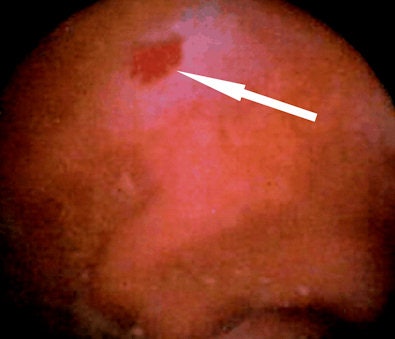

"VCE allows direct visualization of the small bowel mucosa and has a high sensitivity for the detection of flat lesions such as ulcers, angiodysplasias, or arteriovenous malformations, which are lesions beyond the reach of the best CT resolution available," he noted. "VCE shows ulcers and angioectasias that are not visible at CT enteroclysis. A large number of papers have showed that among the variable causes of OGIB, the one most commonly missed at CT enterography was small-bowel angioectasia."

Khalife S, Soyer P, Alatawi A, Vahedi K, et al. Obscure gastrointestinal bleeding: Preliminary comparison of 64-section CT enteroclysis with video capsule endoscopy. Eur Radiol. 2011;21(1):79-86.